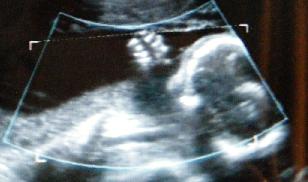

Ujjszopós 2d:

Kép